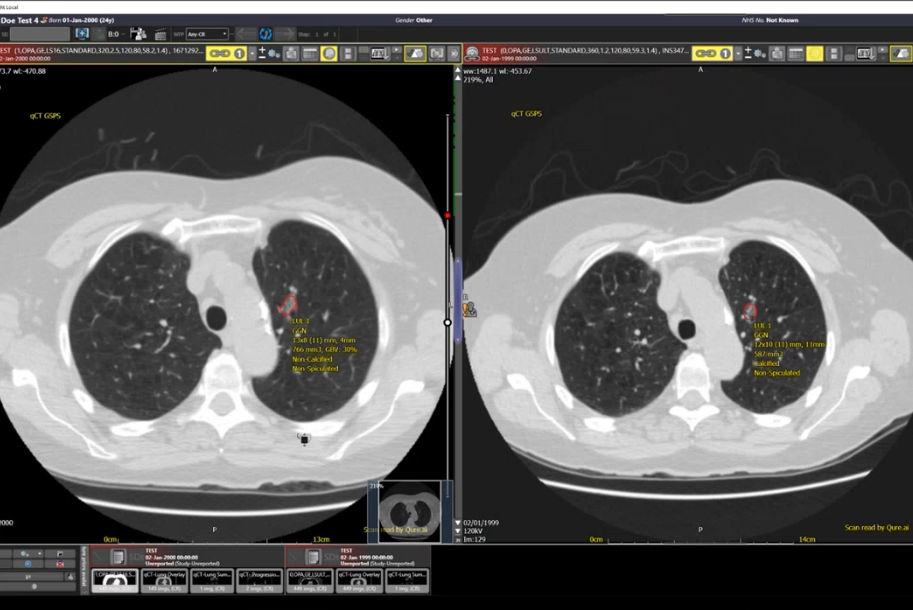

Industry collaboration has been instrumental in leveraging artificial intelligence to enhance radiological operations and patient care. A deal with Lucida Medical is being explored as part of a Topol Fellowship feasibility project to assess the role of AI in triaging prostate cancer patients, and they've received funding to evaluate radiology AI products from Aidoc, Qure.AI, and Radiobiotics. Also, industry-academic collaborations with Mirada Medical and Oxford Heartbeat have been secured from Innovate UK.